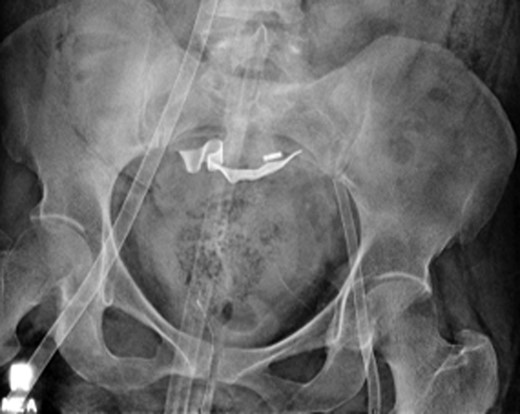

Once stable, imaging confirmed PE (Fig. 2) with a RV to left ventricle (LV) ratio of 2.1 (Fig. 3). The patient was then admitted to the ICU requiring inotropic support. Approximately 4 h later, the patient had concerning features of abdominal compartmental syndrome with increase abdominal distention and bladder pressures >25 mmHg was noted. Repeat imaging showed large volume hemoperitoneum emanating from the left hepatic lobe (Fig. 4). The patient underwent a decompressive laparotomy with a non-anatomic liver resection of segments I and II and temporary abdominal closure. Due to concerns of distal limb ischemia of the arterial cannulation site, an 8-Fr reperfusion cannula was placed in the left superficial femoral artery (SFA).

CTA chest demonstrating significant RV strain with a RV/LV ratio of 2.1.